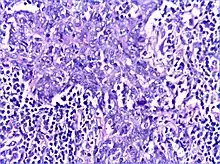

Section from salivary gland showing dense lymphoid infiltrate around and within ductal epithelium-Lympho epithelial lesion (H&E,100X)

There is a marked lymphoplasmacytic infiltration. Lymphoid follicles surround solid epithelial nests, giving rise to the 'epimyoepithelial islands', that are mainly composed of ductal cells with occasional myoepithelial cells. Excess hyaline basement membrane material is deposited between cells, and there is also acinar atrophy and destruction.